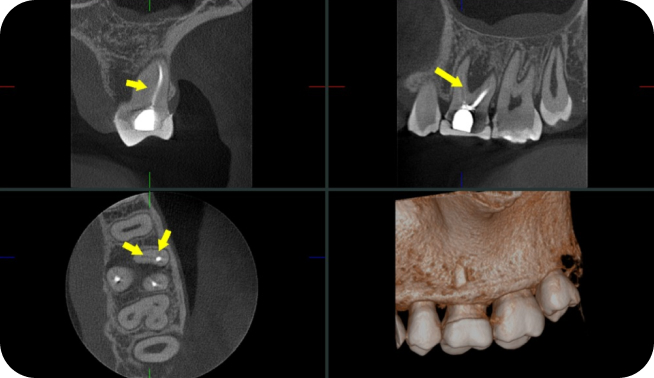

Tomografia Computadorizada

Exame Tridimensional dos Maxilares

Tomógrafo de Altíssima Resolução